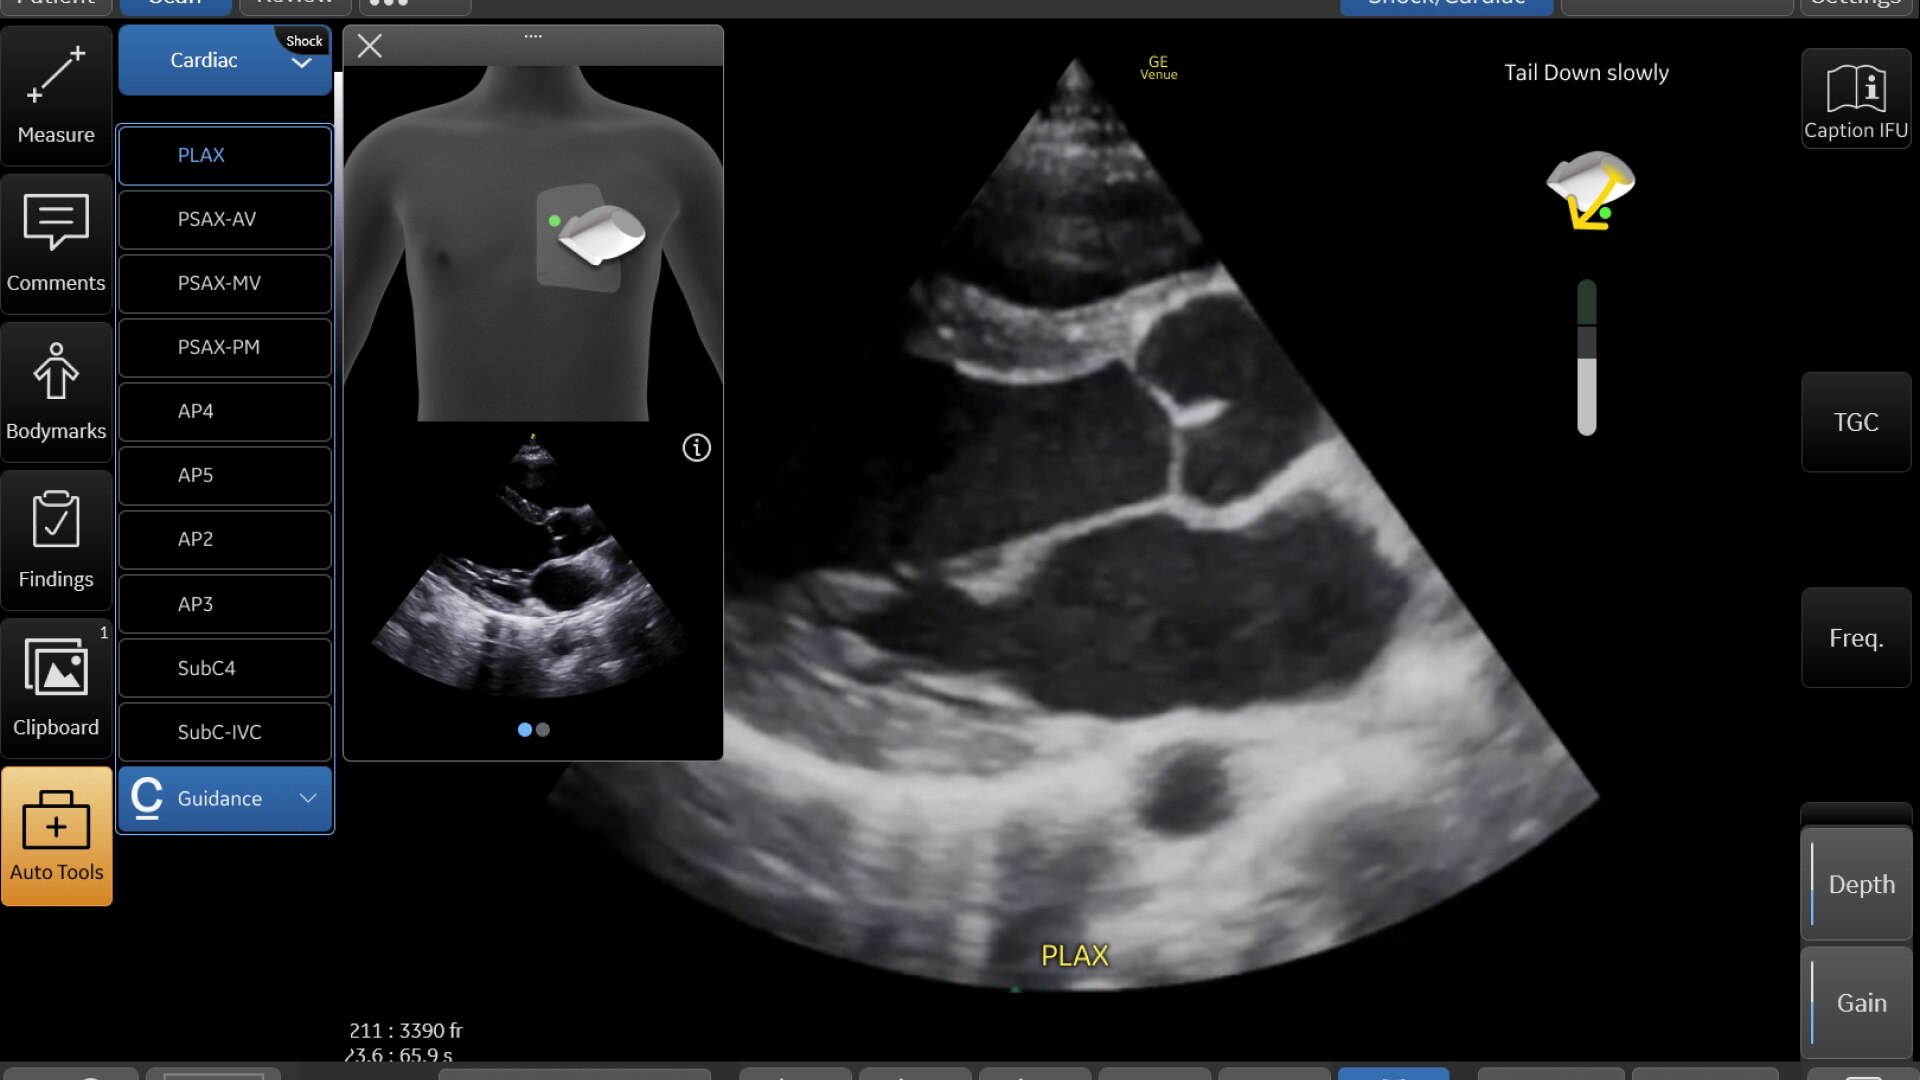

CAPTION GUIDANCE

Scan with confidence: The right tool in the right hands for cardiac ultrasound in critical moments

Thanks to Caption Guidance™ AI-driven software on the Venue Family, even new POCUS users can capture diagnostic-quality cardiac images successfully. The on-screen, AI-based tool aids with turn-by-turn probe placement to capture the needed views.